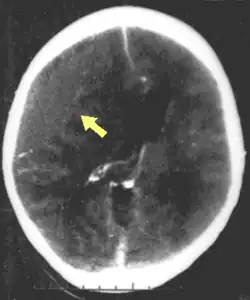

MRI scan showing damage due to brain herniation after TBI[2]

A large percentage of the people killed by brain trauma do not die right away but rather days to weeks after the event;[69] rather than improving after being hospitalized, some 40% of TBI patients deteriorate.[70] Primary brain injury (the damage that occurs at the moment of trauma when tissues and blood vessels are stretched, compressed, and torn) is not adequate to explain this deterioration; rather, it is caused by secondary injury, a complex set of cellular processes and biochemical cascades that occur in the minutes to days following the trauma.[71] These secondary processes can dramatically worsen the damage caused by primary injury[63] and account for the greatest number of TBI deaths occurring in hospitals.[39]

Secondary injury events include damage to the blood–brain barrier, release of factors that cause inflammation, free radical overload, excessive release of the neurotransmitter glutamate (excitotoxicity), influx of calcium and sodium ions into neurons, and dysfunction of mitochondria.[63] Injured axons in the brain's white matter may separate from their cell bodies as a result of secondary injury,[63] potentially killing those neurons. Other factors in secondary injury are changes in the blood flow to the brain; ischemia (insufficient blood flow); cerebral hypoxia (insufficient oxygen in the brain); cerebral edema (swelling of the brain); and raised intracranial pressure (the pressure within the skull).[72] Intracranial pressure may rise due to swelling or a mass effect from a lesion, such as a hemorrhage.[51] As a result, cerebral perfusion pressure (the pressure of blood flow in the brain) is reduced; ischemia results.[39][73] When the pressure within the skull rises too high, it can cause brain death or brain herniation, in which parts of the brain are squeezed by structures in the skull.[51]